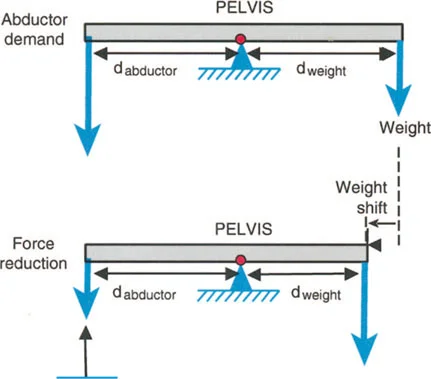

أمثلة أخرى رئيسية للتشوهات الديناميكية تشمل "الورم الفخذي المفرط" (Severe Femoral Anteversion) و "الورك الأفحج" (Coxa Vara). في كلتا هاتين الشذوذات المعمارية، يتم تقصير الطول الفيزيائي لذراع الرافعة لعضلات المبعدة (Abductor muscles) بشكل مرضي بسبب التشوه العظمي نفسه. قد تكون عضلة الألوية الوسطى (Gluteus Medius) صحية تمامًا، ومعصبة جيدًا، وقادرة على توليد قوة بيولوجية طبيعية، لكنها تعاني من خلل وظيفي سريري عميق لأن ميزتها الميكانيكية قد سُلبت بسبب الهندسة الهيكلية المتغيرة. هذه الفئة الفرعية المحددة من الأمراض تُعرف باسم "تشوه في طول ذراع الرافعة".

- الورك الأفحج (Coxa Vara): تشوه خلقي أو تطوري في عظم الفخذ يؤدي إلى تقصير ذراع الرافعة لعضلات الورك المبعدة، مما يضعف قدرتها على تثبيت الحوض.

- عرج ترندلنبورغ (Trendelenburg Lurch): في حالات ضعف عضلات الورك المبعدة (مثل الورك الأفحج)، يميل الحوض إلى السقوط على الجانب المقابل أثناء الوقوف على ساق واحدة، مما يؤدي إلى مشية متمايلة.